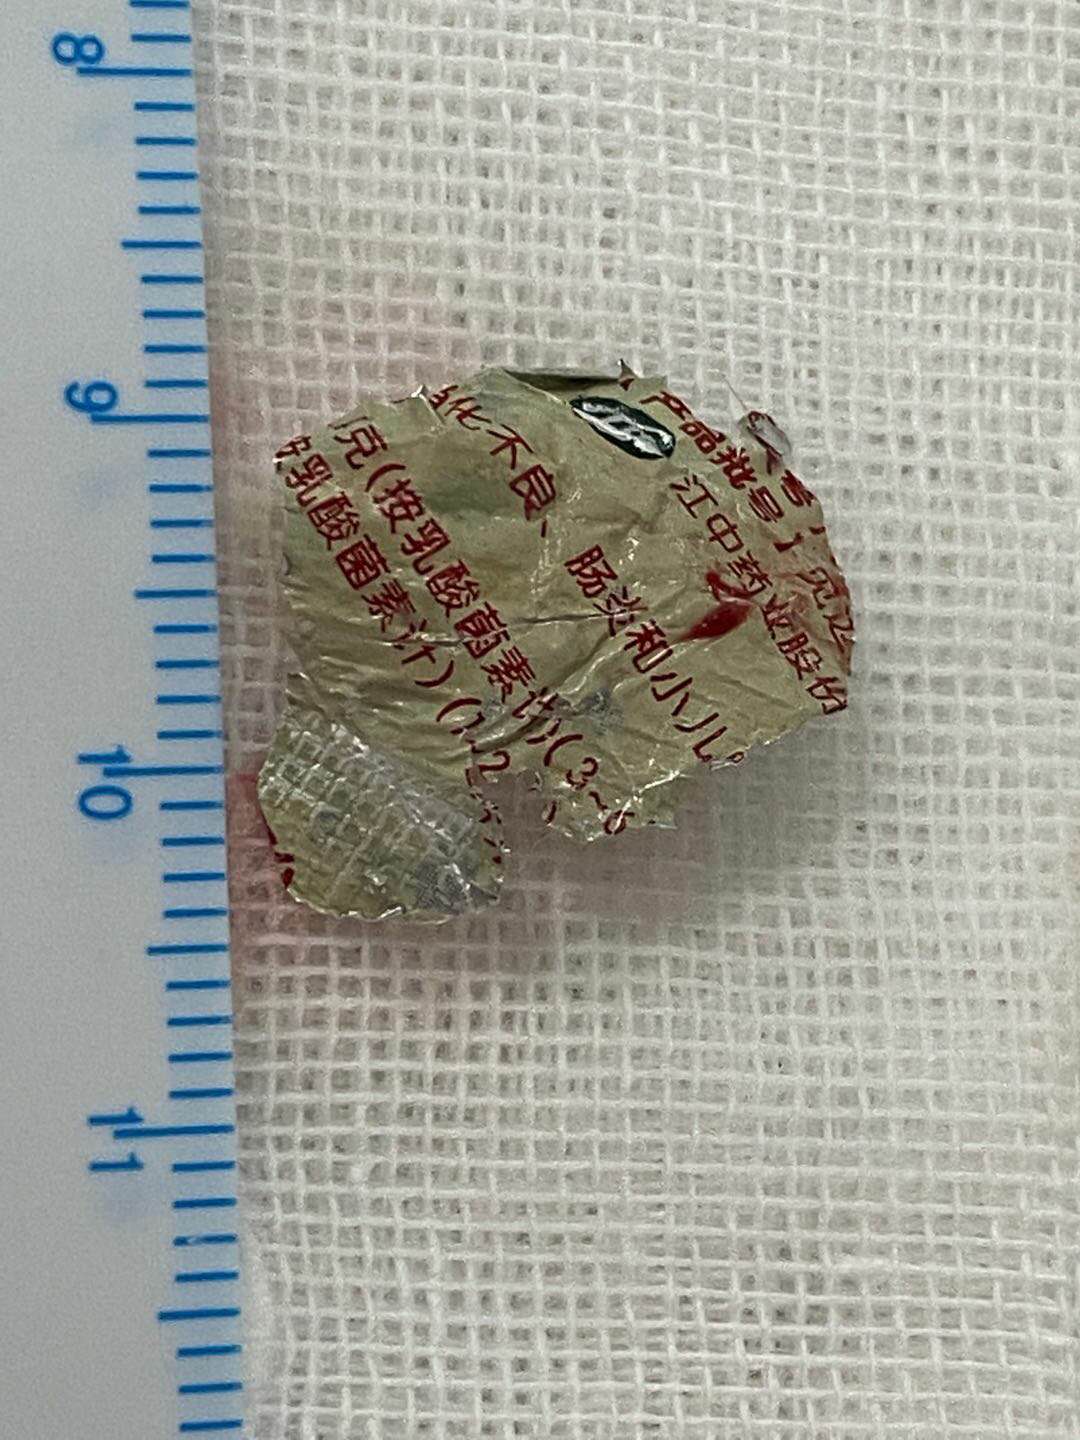

在完成气管镜检查后,介入组医生又对食道进行探查,结果更让人吃惊——安安的食道中段内有一个印着“小儿”两字的不明物体嵌入食管壁。医生反复追问家长有无误食特殊“食物”,家长本来对气管内何时呛入异物都想不起来,听说食道内也有异物,更是直摇头。

这个带着“小儿”字样的异物是什么?是如何产生的呢?它为什么会在这里?而难点不止于此,最致命的问题是CT影像上疑似异物嵌入食管壁,距离血管很近,取出时稍有不慎就会碰到血管引发大出血。

一个锡纸药品包装盒嵌入食管

这个标着“小儿”字样的异物,原是儿童常见口服药物的锡纸包装袋,而且边缘锋利,幸而手术快、准、稳,没有划伤患儿食管。